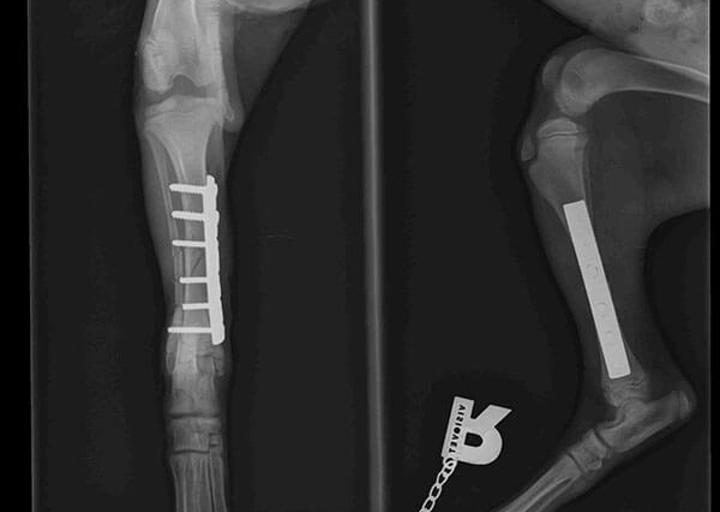

Natürlich wurde Ray so schnell wie möglich operiert. Die OP Kosten belaufen sich auf 240 €.